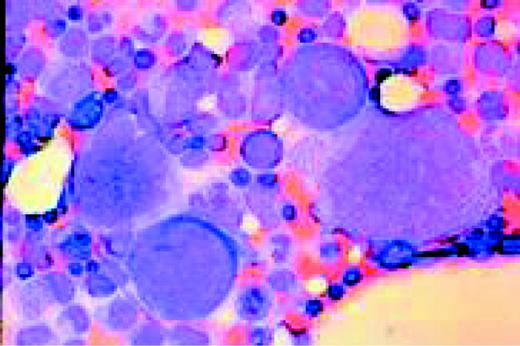

Slide L39

Multiple myeloma, bone marrow aspirate. Virtually every cell in the field is a neoplastic plasma cell. They show nuclear eccentricity, pleomorphism, and a tendency to stick together in clumps.FIG39